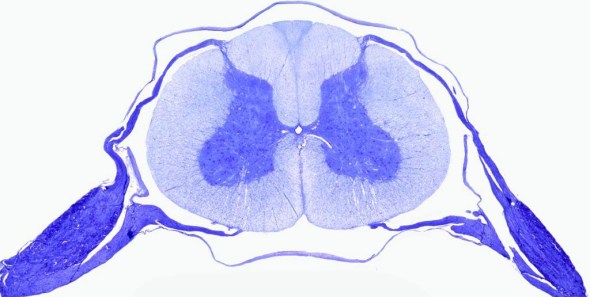

Know your spinal cord – The landmarks

A human cervical spinal cord slice. Once you’ve read this post, you should be able to identify the major parts and tell which side is the front of the cord.

Welcome to day thirty-three in our series. For those of you who are just finding us, we have every one of these posts in our neuroanatomy category in reverse chronological order. Today we’re going to backtract (get it?) a little and go over something basic, but something we’ve skipped over to this point. We never really talked about the landmarks of a spinal cord slice. So today, we are going to take a detour and go over spinal cord features.